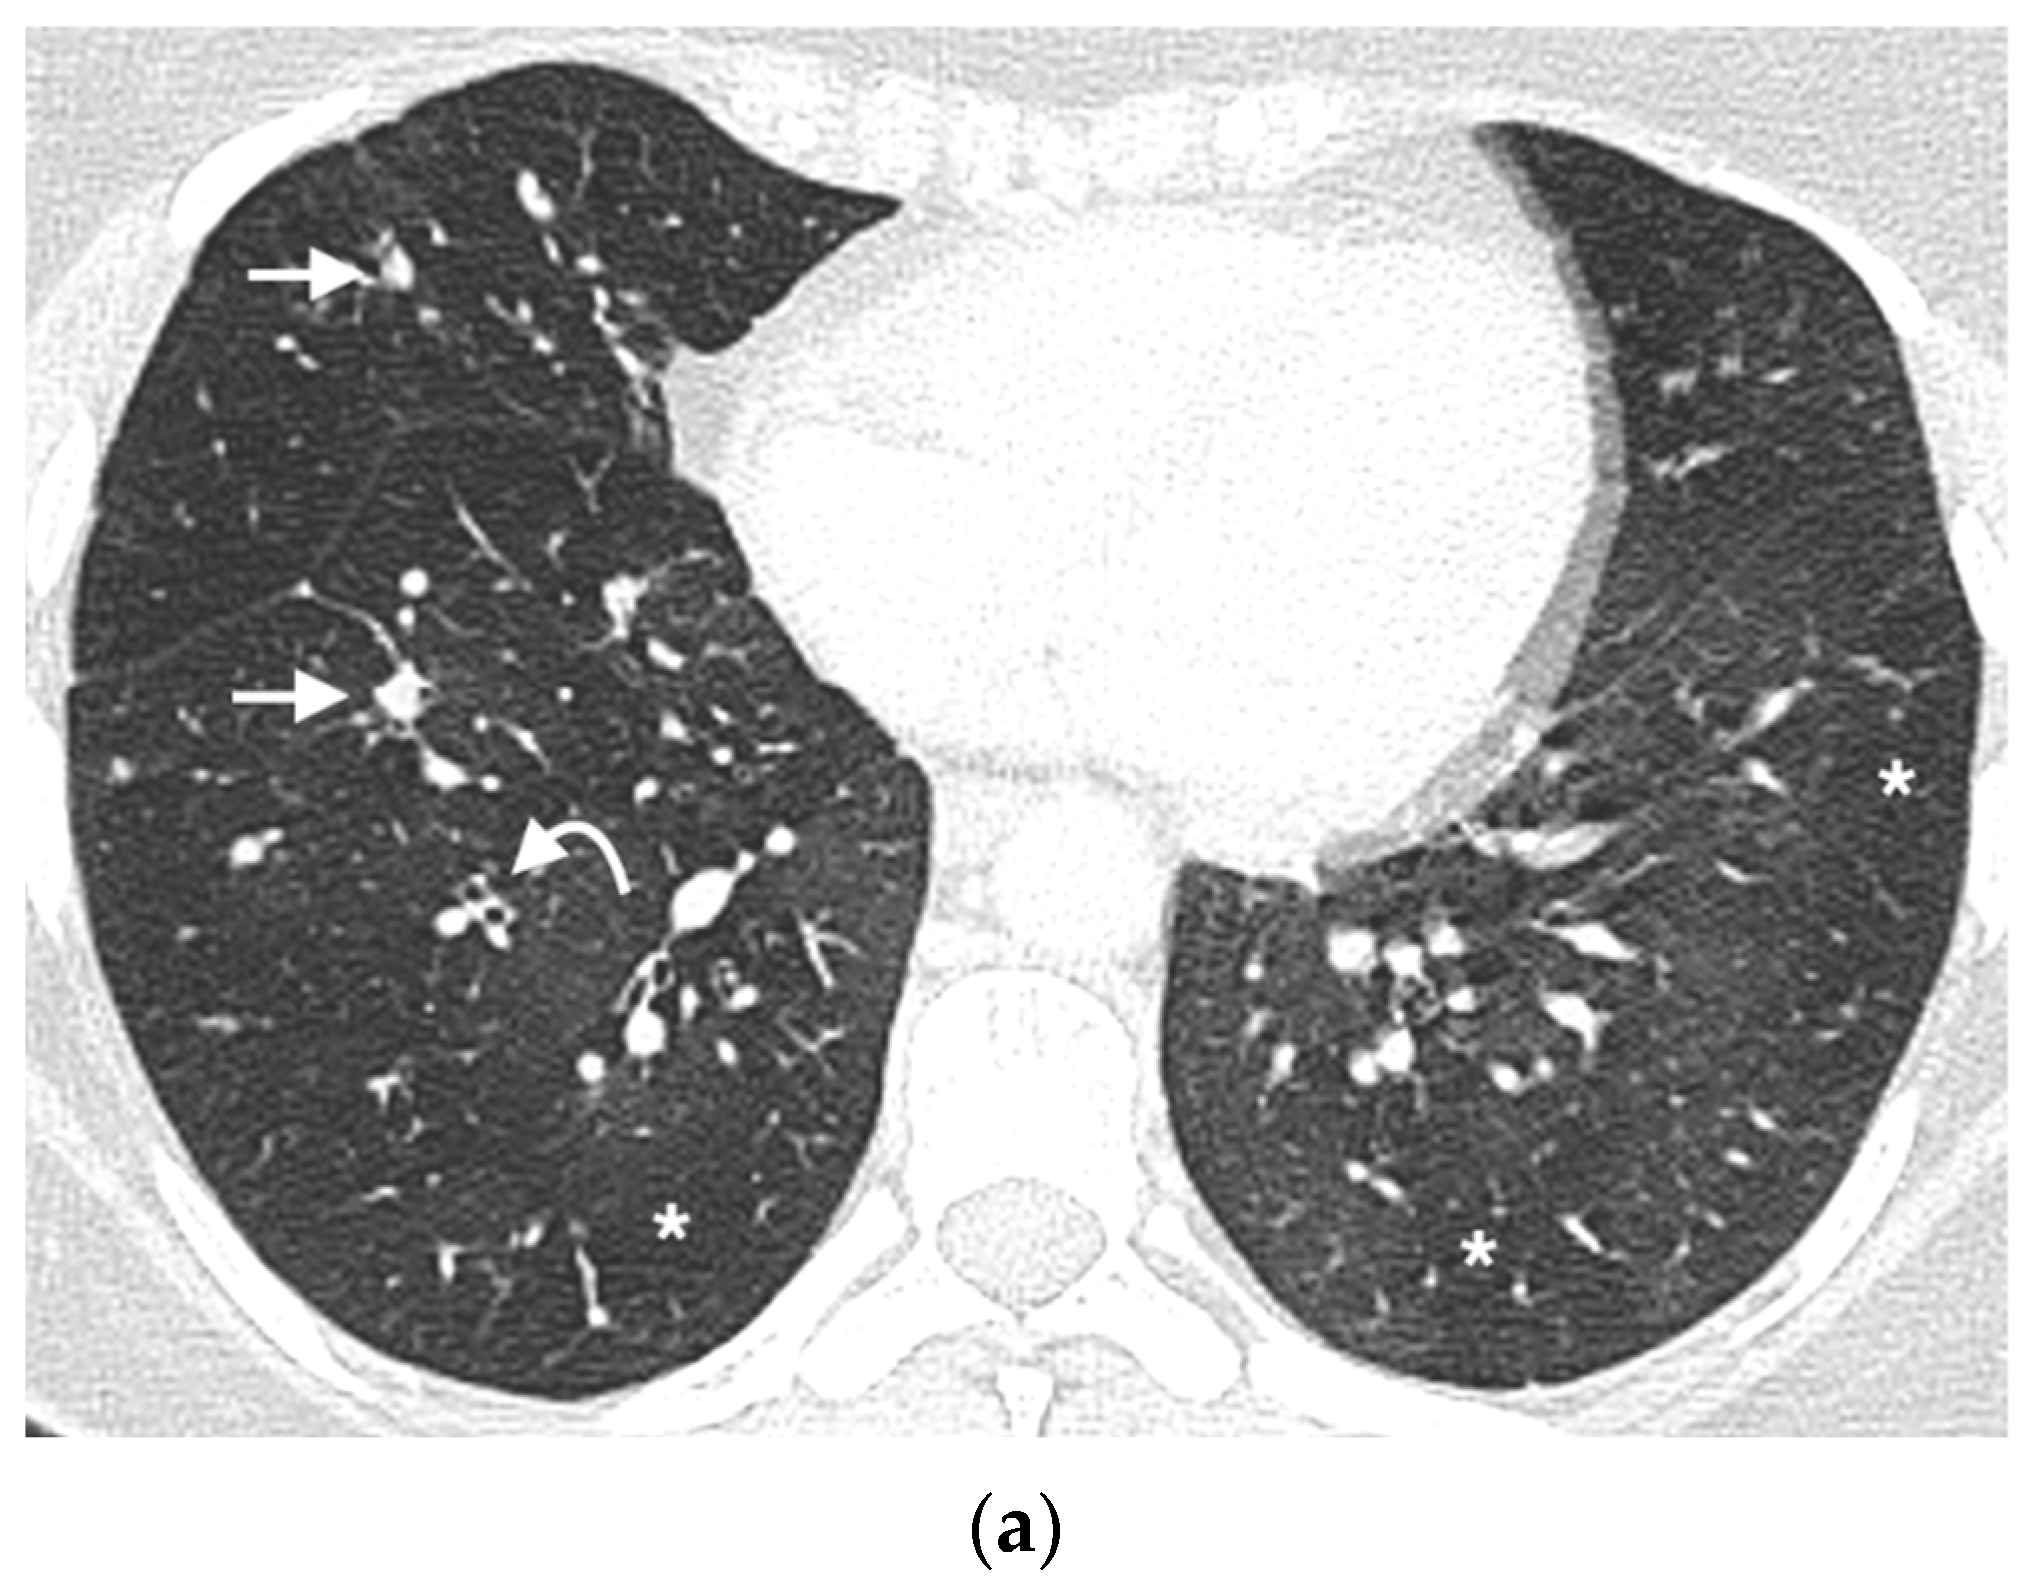

:1. Introduction

3. Results

3.3. Mosaic Attenuation

3.4. Nodule Characteristics